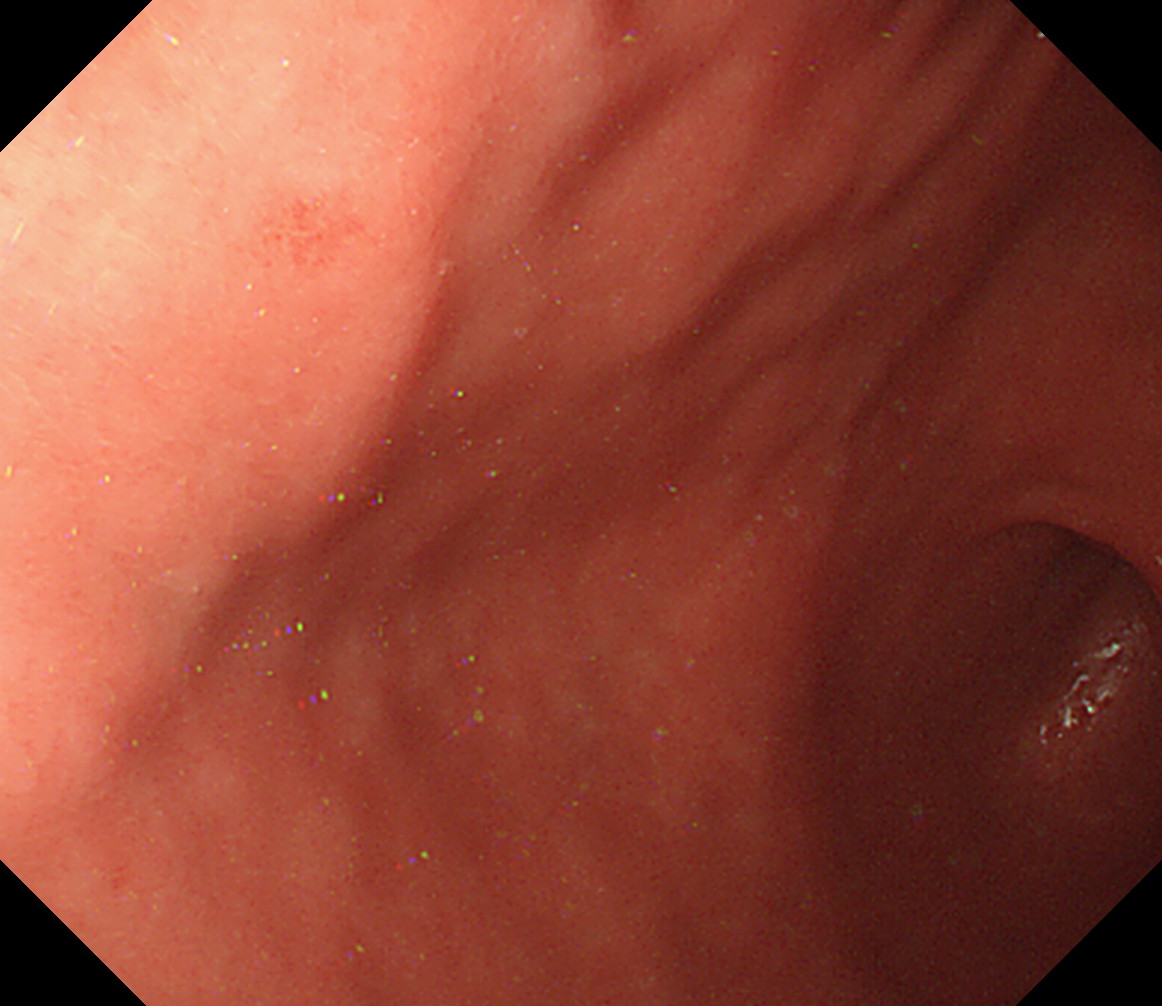

24 体下部後壁 引き上げて

後壁から反時計回り

接線になり見逃しやすい部位です

体下部後壁